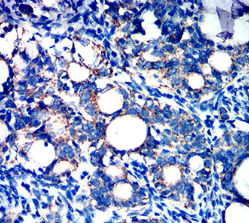

IHC    1/200 - 1/1000